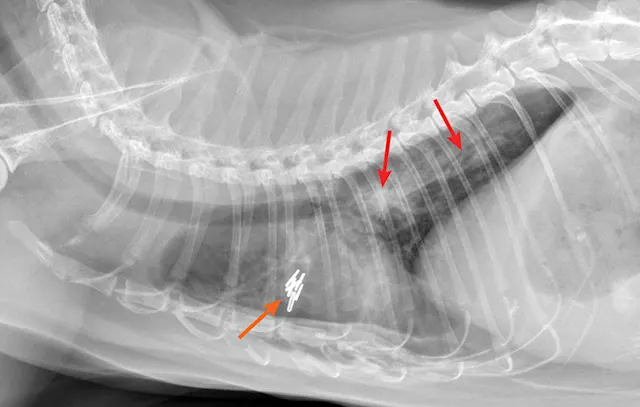

Thoracic radiographs may reveal a bronchointerstitial pattern, alveolar infiltrates, a diffuse bronchial pattern, and (rarely) pleural effusion (Figure 5).10,11 Diagnosis may be made via identification of first-stage larvae from airway cytology specimens or fecal samples. In clinical practice, false-negative fecal samples have been appreciated due to intermittent fecal shedding. Repeated testing may increase sensitivity but has not been evaluated. Therefore, any patient suspected of potential lungworm should be treated. Less common lungworms have been reported in cats, including Paragonimus spp12-14 and Capillaria spp.15

FIGURE 5A

Radiograph of aelurostrongylus abstrusus infection (lungworm). Note the diffuse bronchial pattern (orange arrows), patchy poorly defined soft-tissue nodules (red arrows), and right middle lung lobe alveolar disease (yellow arrow). This pattern could be confused with feline asthma in this case; however, the right middle lung does not appear atelectatic but instead infiltrated. Fine-needle aspiration of the right middle lung lobe confirmed larvae.